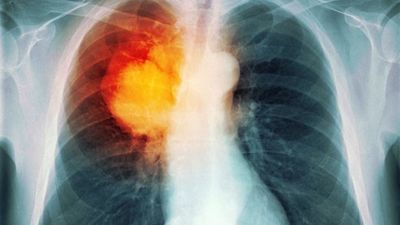

A e rrisin vitaminat e zakonshëm rrezikun e kancerit në mushkëri

Meshkujt, dhe veçanërisht meshkujt duhanpirës, duket se janë më të prirë të diagnostikohen me kancer të mushkërive nëse konsumojnë doza të mëdha të vitaminës B6 dhe B12.

Sipas hulumtimeve, meshkujt të cilët merrnin këto suplemente të vitaminave kishin pasur një rrezik thuajse dyfish më të lartë të zhvillimit të kancerit në mushkëri, transmeton Telegrafi.

Ndërsa për meshkujt duhanpirës, rreziku kishte qenë deri në katërfish më i lartë.

“Dozat e larta të suplementeve me vitamina B6 dhe B12 nuk duhet të merren për parandalimin e kancerit në mushkëri, e veçanërisht te meshkujt, sepse mund të shkaktojnë dëme”, ka treguar autori i këtij studimi Theodore Brasky.

Sidoqoftë, studimi nuk ka qenë i dizajnuar të dëshmojë shkaktarin dhe efektin mes vitaminave dhe kancerit të mushkërive, por ka treguar vetëm një ndërlidhje mes tyre. /Telegrafi/